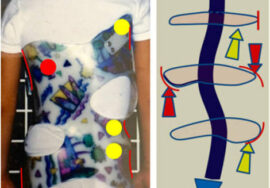

نموذج توتر الأعصاب في اعوجاج العمود الفقري الطفولي

شرح نموذج روث (Roth) لتوتر الأعصاب في الاعوجاج الطفولي يوضح أن الحبل الشوكي القصير والمتوتر يخلق قوة تسحب العمود الفقري إلى الداخل لتخفيف التوتر. النتيجة هي الانحناءات التي نراها في صور الأشعة للأطفال المصابين بالاعوجاج.

بعبارة أبسط: العمود الفقري يحاول “الانحناء” ليقلل من توتر الحبل الشوكي، وليس فقط بسبب العظام أو العضلات. هذه النظرية تفسر لماذا بعض الانحناءات تستمر في التفاقم حتى مع العلاج التقليدي إذا لم يتم التعامل مع شد الحبل الشوكي.